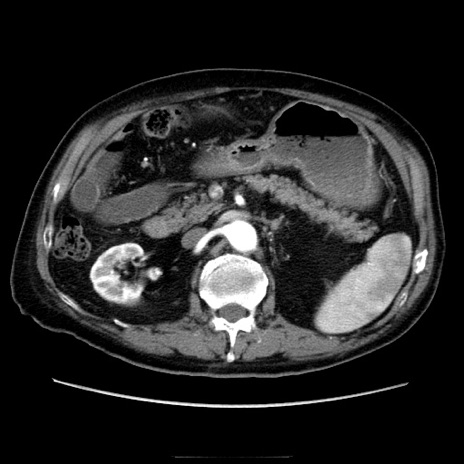

症例21(横断像)

【症例】70歳代男性

【主訴】腹痛

【現病歴】肝硬変・肝細胞癌にてかかりつけの方。約9時間前に食後より腹痛出現。症状が徐々に増悪し、嘔吐出現したため来院。

【既往歴】肝硬変、肝細胞癌(RFA、TACE後)

【身体所見】意識清明、表情苦悶様、BT 36℃、BP 129/78mmHg、P 88bpm、SpO2 97%(RA)、右上腹部から心窩部にかけて圧痛あり、反跳痛なし、筋性防御あり。

【データ】WBC 5800、CRP 0.16